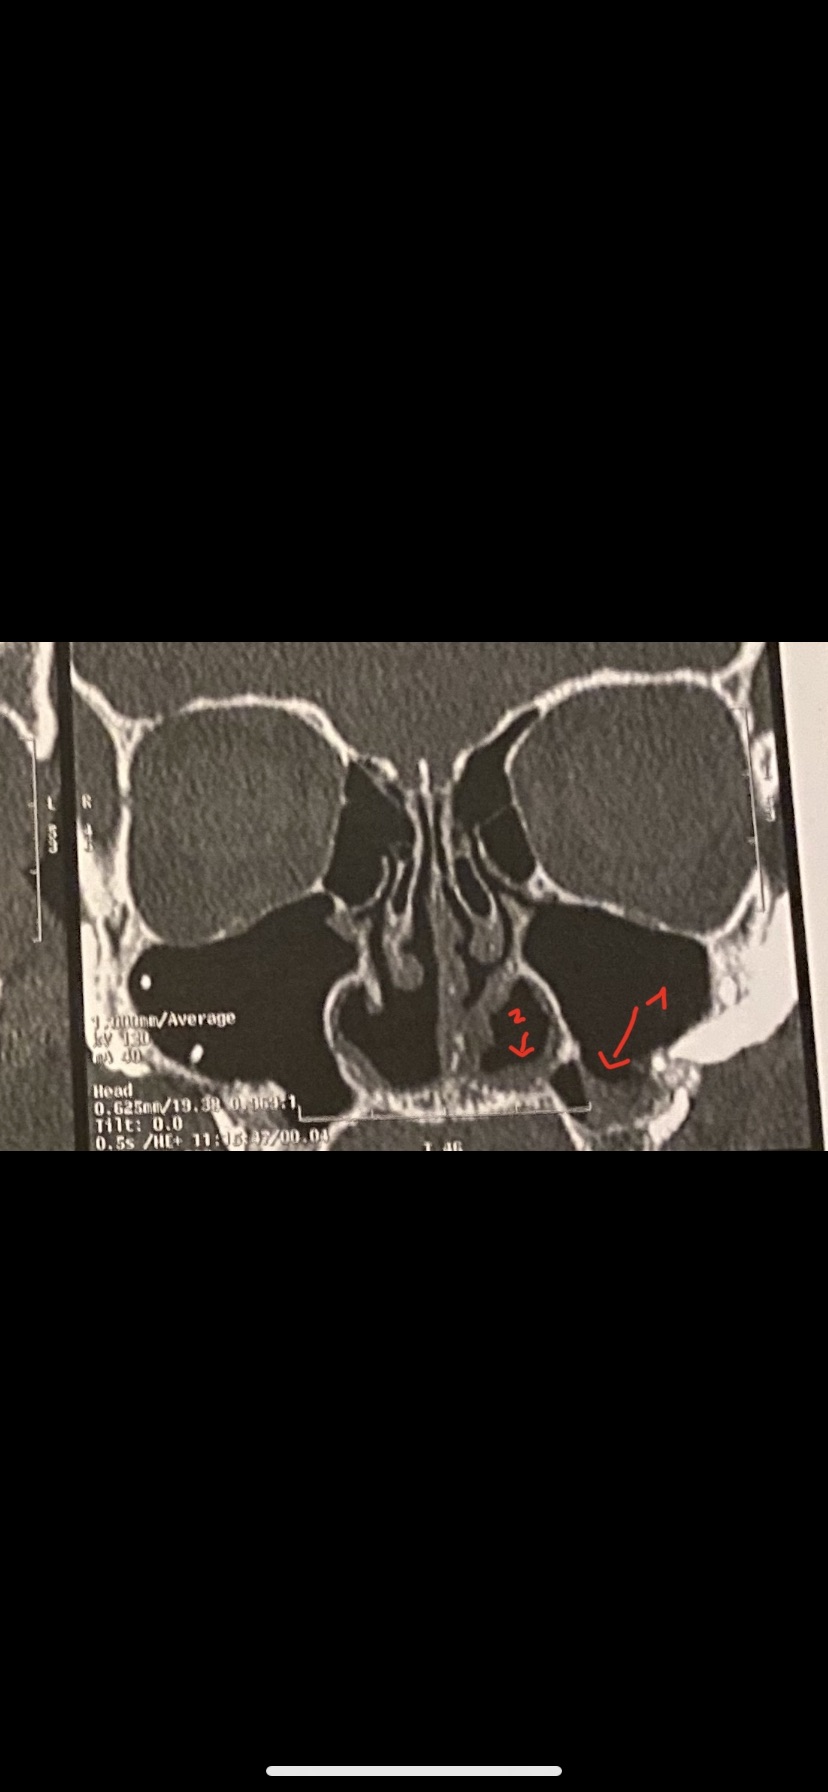

Hello Dr, I have pain in my nose after rhinoseptoplasty (a lot of grafts were placed), I want to know regarding the scan, what are the spurs pointed with a red arrow? Could it provoke pain? I also would like to know if the second image show scar tissue in my sinus or something else I know I have a synechia that I will need removed because it's causing congestion.. Thank you in advance